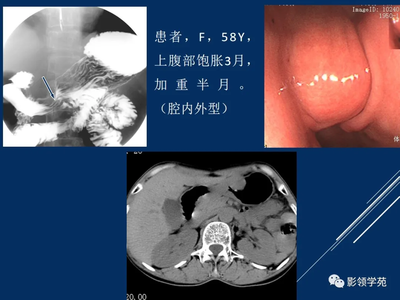

你好!如何诊断胃间质瘤?只有胃镜看到的不能确诊。建议进行超声内镜和薄层增强ct检查。如果方便的话,你可以带着所有的资料来我们消化肿瘤科门诊看。谢谢你的关心。一般不会引起。是副作用吗?首先,胃间质瘤不会引起贫血。这个东西可以手术切除,算是良性病变。防治贫血推荐多糖铁复合物(宏远达),安全易吸收,对胃肠道无刺激,副作用小。

你好!根据你提供的信息,是胃间质瘤复发。你复查过胃镜吗?盆腔检查了吗?如果检查只发现单发肿瘤,可以考虑手术切除。但术后应口服格列卫(建议服药前检测CKIT基因突变)。你可以申请加入慈善总会的援助项目。建议去看当地的肿瘤专科医生。谢谢你的关心。